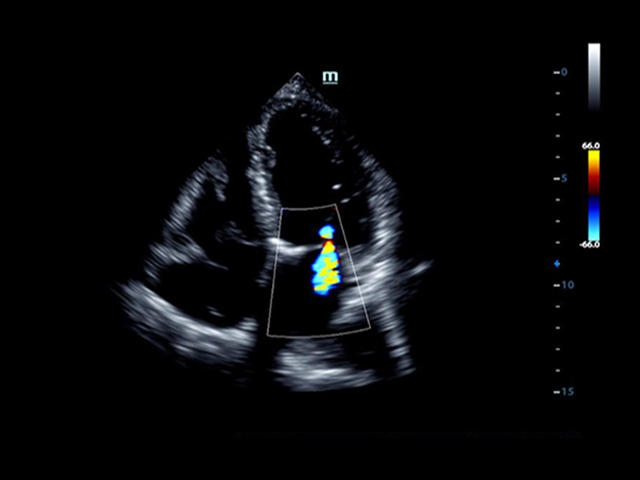

Mindray DC-8 Exp – это ультразвуковой аппарат с архитектурой mQuadro и функцией эластографии Natural Touch. Он оснащен высококлассным 21-дюймовым TFT-монитором с разрешением Full HD. Данный аппарат представляет интерес для специалистов, занимающихся обследованием мягких тканей с использованием эластографии. Режим объемного 4D-сканирования позволяет получать максимально точные диагнозы, сокращая количество неэффективных процедур.

Mindray DC-8 Exp оснащен новым поколением датчиков с увеличенным количеством элементов и инновационной технологией "3T". Это позволяет достичь высокой детализации и качества изображения. Благодаря новейшей технологии iFlow, можно визуализировать даже самые мелкие сосуды и кровеносные пути.

• LVO - опция проведения исследования левого желудочка сердца с применением контрастных веществ;